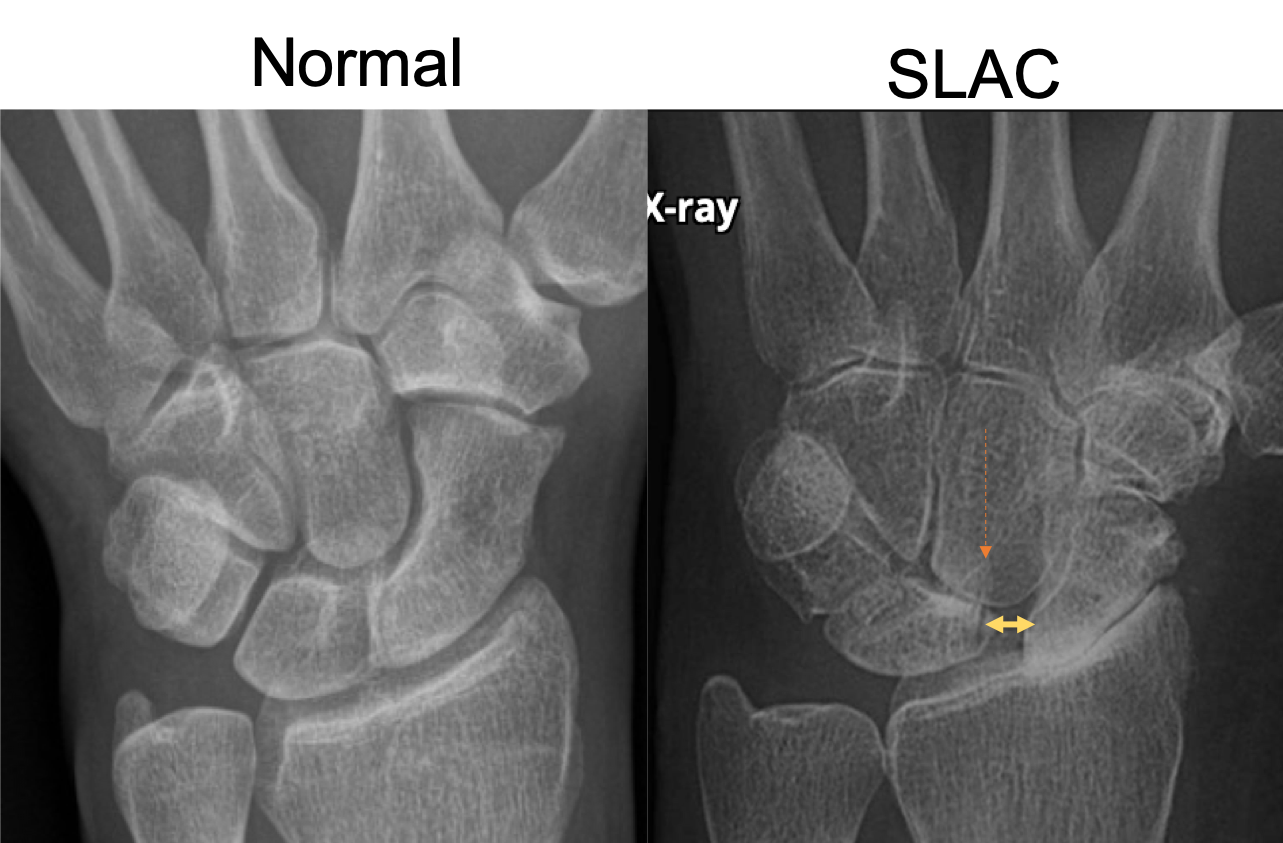

What is SLAC wrist?

Scapholunate advanced collapse (SLAC) = widening of the scapholunate interval and proximal migration of the capitate

Terry-Thomas sign refers to an increase in the scapholunate space on an AP radiograph of the wrist (or coronal CT).

The increased distance indicates scapholunate dissociation (often with rotary subluxation of the scaphoid) due to ligamentous injury. There is no consensus as to what measurement constitutes widening, but a cut-off of 3 or 4 mm is reasonable in most cases.

SLAC wrist is associated with:

OA

CPPD

Chronic untreated scapholunate dissociation